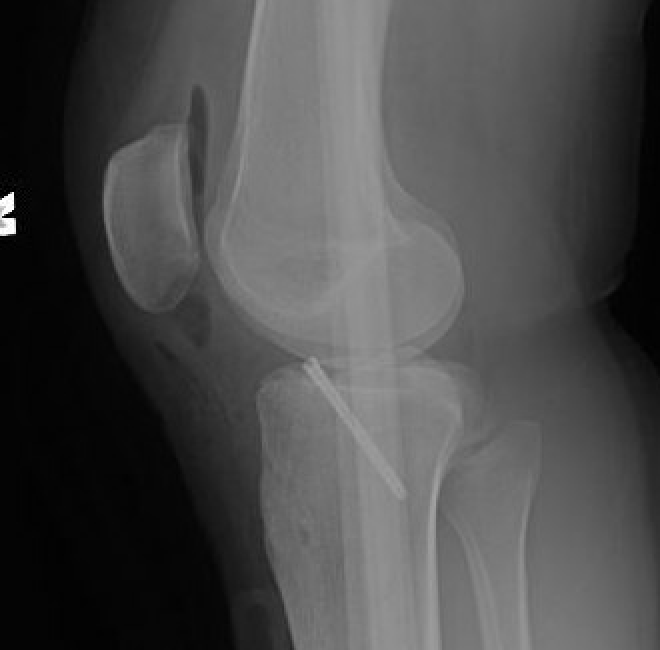

Xray

Xray showing likely Type II with anterior hinging

Xray demonstrating reduction of fragment with knee in hyperextension and in cast